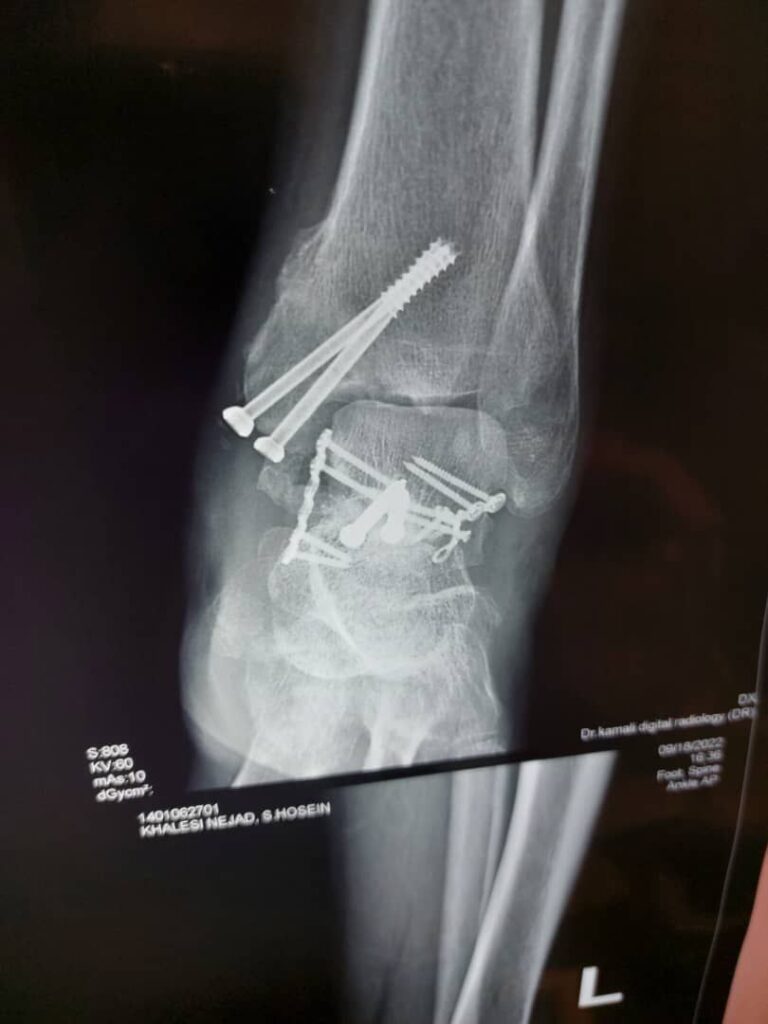

-اعمال جراحی ( شکستگی ها , تعویض مفصل )

در اولین ملاقات، ارتوپد برای تشخیص وضعیت فرد اقداماتی را انجام می‌دهد. این اقدامات به‌طور معمول شامل انجام معاینه فیزیکی و تصویربرداری اشعه ایکس است. گاهی اوقات، ارتوپد برای کمک به تشخیص یا درمان این بیماری از روش‌هایی مانند تزریق استفاده می‌کند. در برخی موارد، آزمایشات تکمیلی برای تأیید تشخیص لازم است.

اشعه ایکس رایج‌ترین و گسترده‌ترین روش تصویربرداری تشخیصی است. یک دکتر ارتوپد اغلب تصویربرداری اشعه ایکس را در محل کار خود انجام می‌دهد؛ این اقدام به او اجازه می‌دهد برخی شرایط را در هنگام ویزیت شخص تشخیص دهد. برخی از آسیب‌های حاد، مانند شکستگی و دررفتگی، به اقدامات ارتوپدی نیاز دارد تا استخوان یا مفصل را به حالت قبل بازگردانده و با استفاده از آتل، گچ یا بریس ثابت شود.